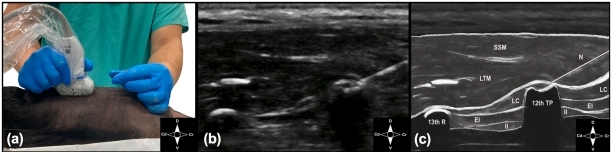

В исследовании были задействованы одна кошка в возрасте 1 год и 5 месяцев, а также два свежих трупа – кошки и собаки породы метис. Всем биологическим моделям со средней массой тела 4 ± 0,5 кг, без травм грудной клетки и с индексами кондиции тела 5–6/9 была проведена ESP-блокада с использованием УЗ-навигации, после чего проводилась компьютерная томография (КТ) для оценки распределения контрастного препарата в межфасциальном, паравертебральном и эпидуральном пространствах. Исследование было проведено с согласия владельцев всех животных. Гибель двух животных не была связана с необходимостью проведения исследования и была опосредована другими причинами. Проведение исследования не повлияло на состояние здоровья живого животного: осложнений после анестезии, КТ и введения контрастного препарата в межфасциальное пространство в процессе длительного периода наблюдения не выявлено.КТ проводил и оценивал врач визуальной диагностики (модель компьютерного томографа Philips MX16). Для ультразвуковой навигации использовался аппарат УЗИ (SonoScape ST-190), оснащенный линейным датчиком с частотой 7,5 МГц.

При выполнении блокады и рентгенографического исследования биологические модели располагались в дорсовентральном положении. Процедура проведения ESP-блокады под ультразвуковым контролем включала введение контрастного препарата «Омнипак» (350 мг/мл) в межфасциальное пространство на уровне Th5-Th6 в дозе 0,4 мл/кг после предварительной гидродиссекции. Сразу после выполнения блокады проводилась КТ грудной клетки для оценки распределения контрастного препарата в межфасциальном, паравертебральном и эпидуральном пространствах.